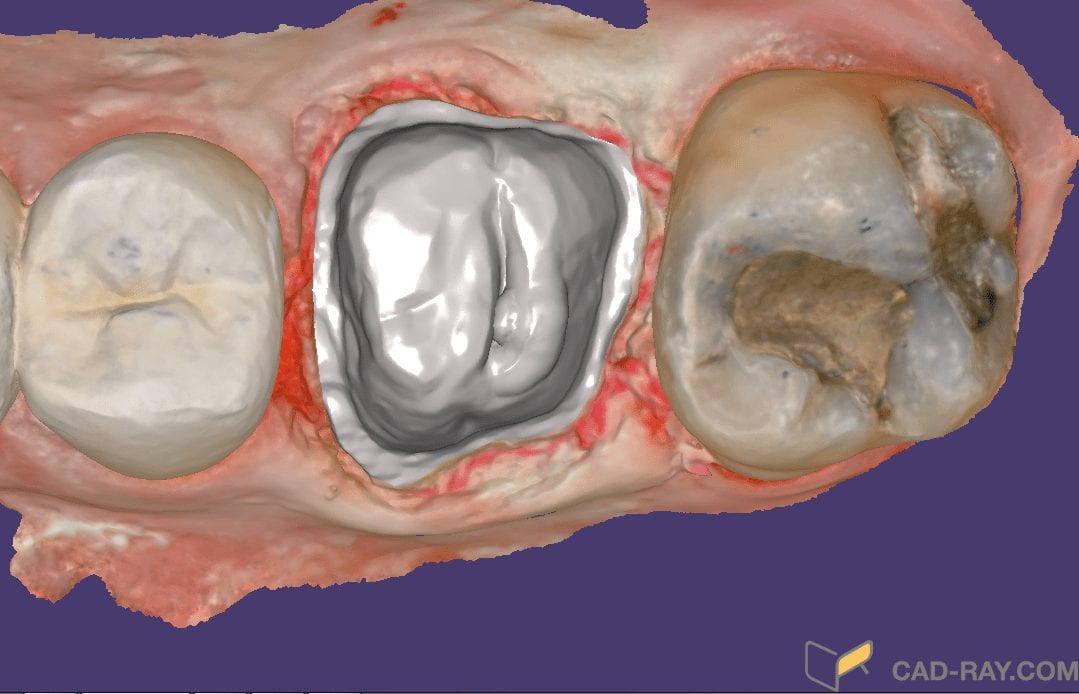

Quickest Way to Design and Mill a Case

February 13, 2019One of the most popular design techniques in digital dentistry is copying the pre-existing morphology of a restoration. When it is in occlusion and has desirable contours, you can image […]